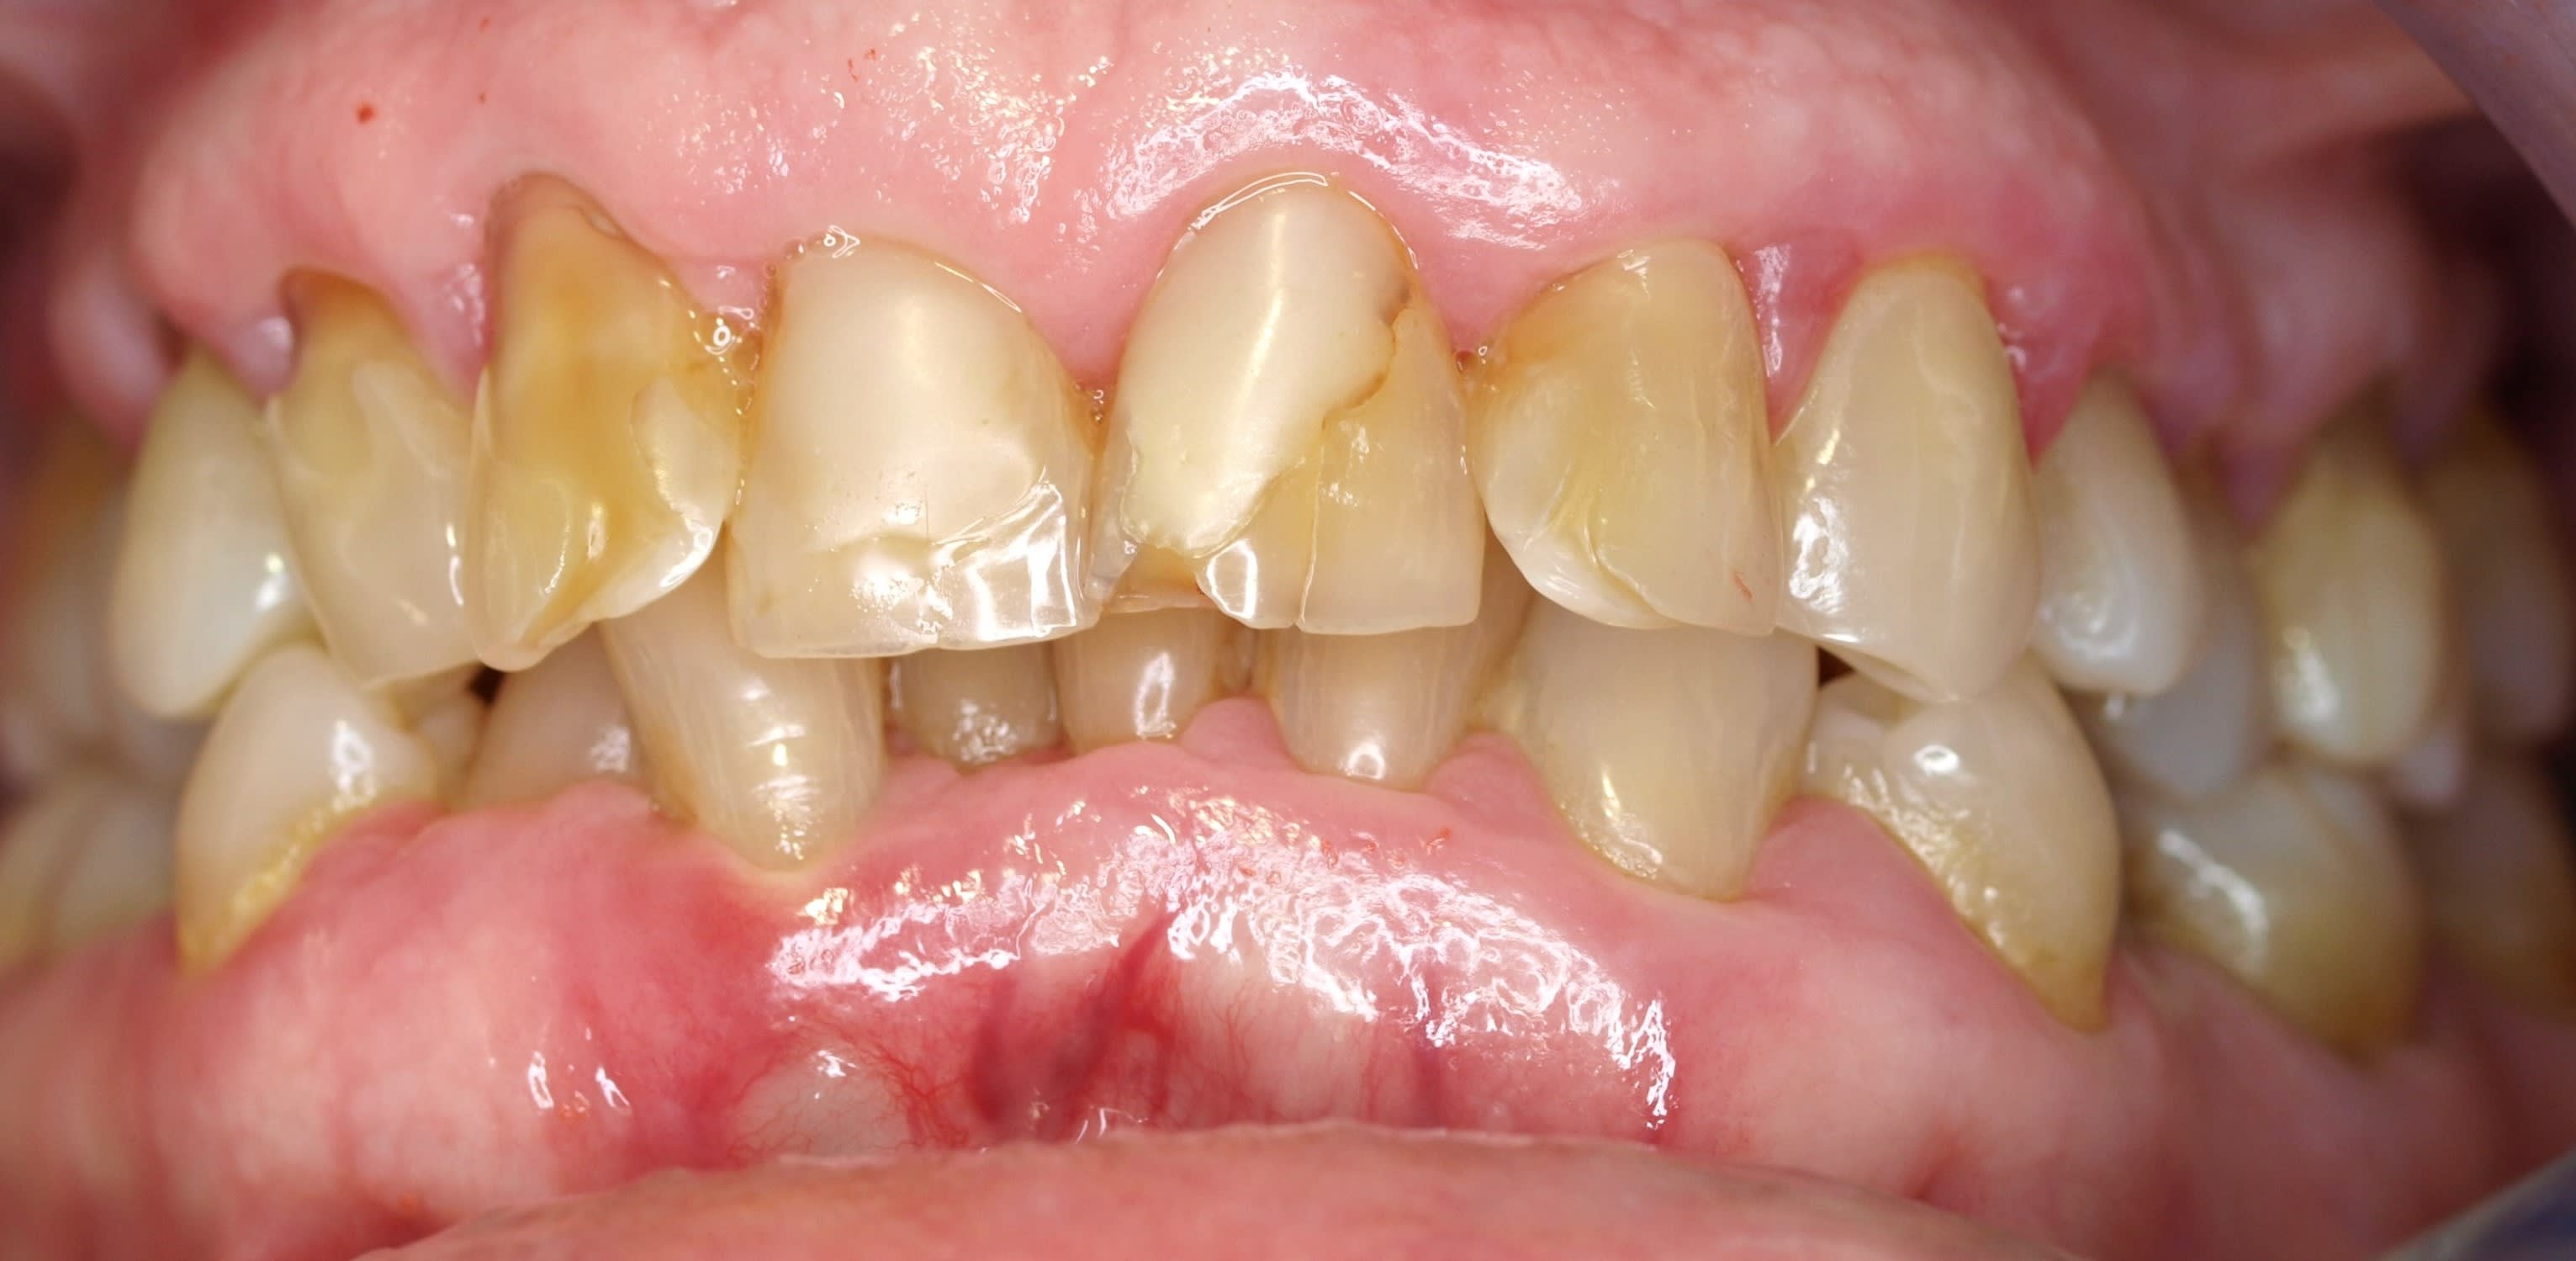

ici il y a manifestement un désordre occlusal , du bourgeon printanier , et une ligne des collets qui suit le cac 40 .

là on est après la préparation initiale cad un détartrage , quoi .

plus la dent est en avant - il y a d os et + le collet migre en apical . en haut comme en bas